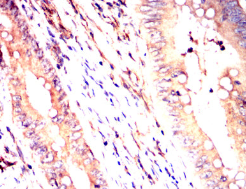

IHC    1/200 - 1/1000